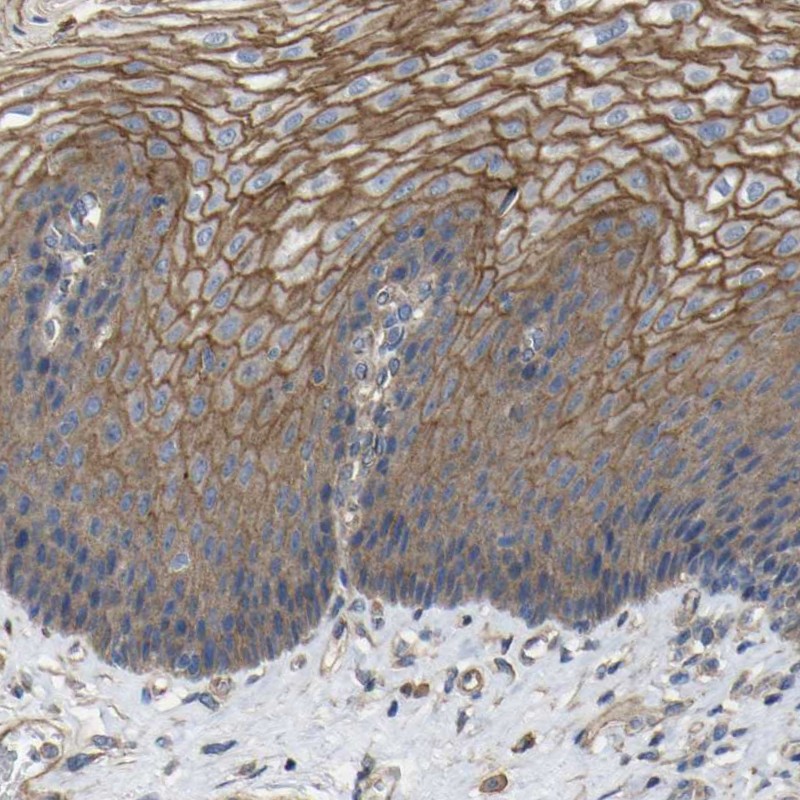

Immunohistochemical staining of human esophagus shows strong membranous positivity in squamous epithelial cells.